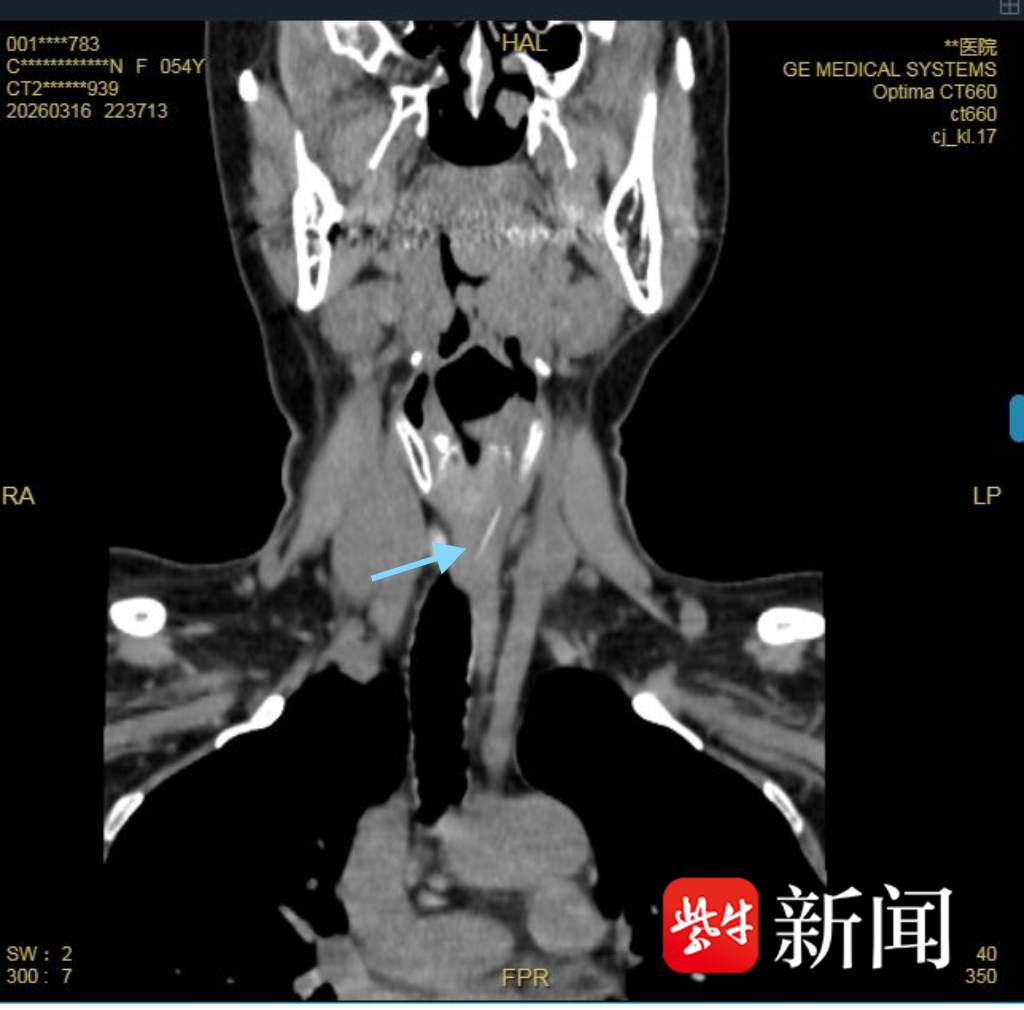

CT显示异物嵌顿

为寻求进一步治疗,陈女士转入江苏省人民医院消化内科。CT显示,鱼刺位于食管上段平C6-7椎体水平,长度约21mm,已完全嵌入食管组织内,致食管局部炎症增厚,加之患者有脑膜瘤手术史,病情更为复杂。